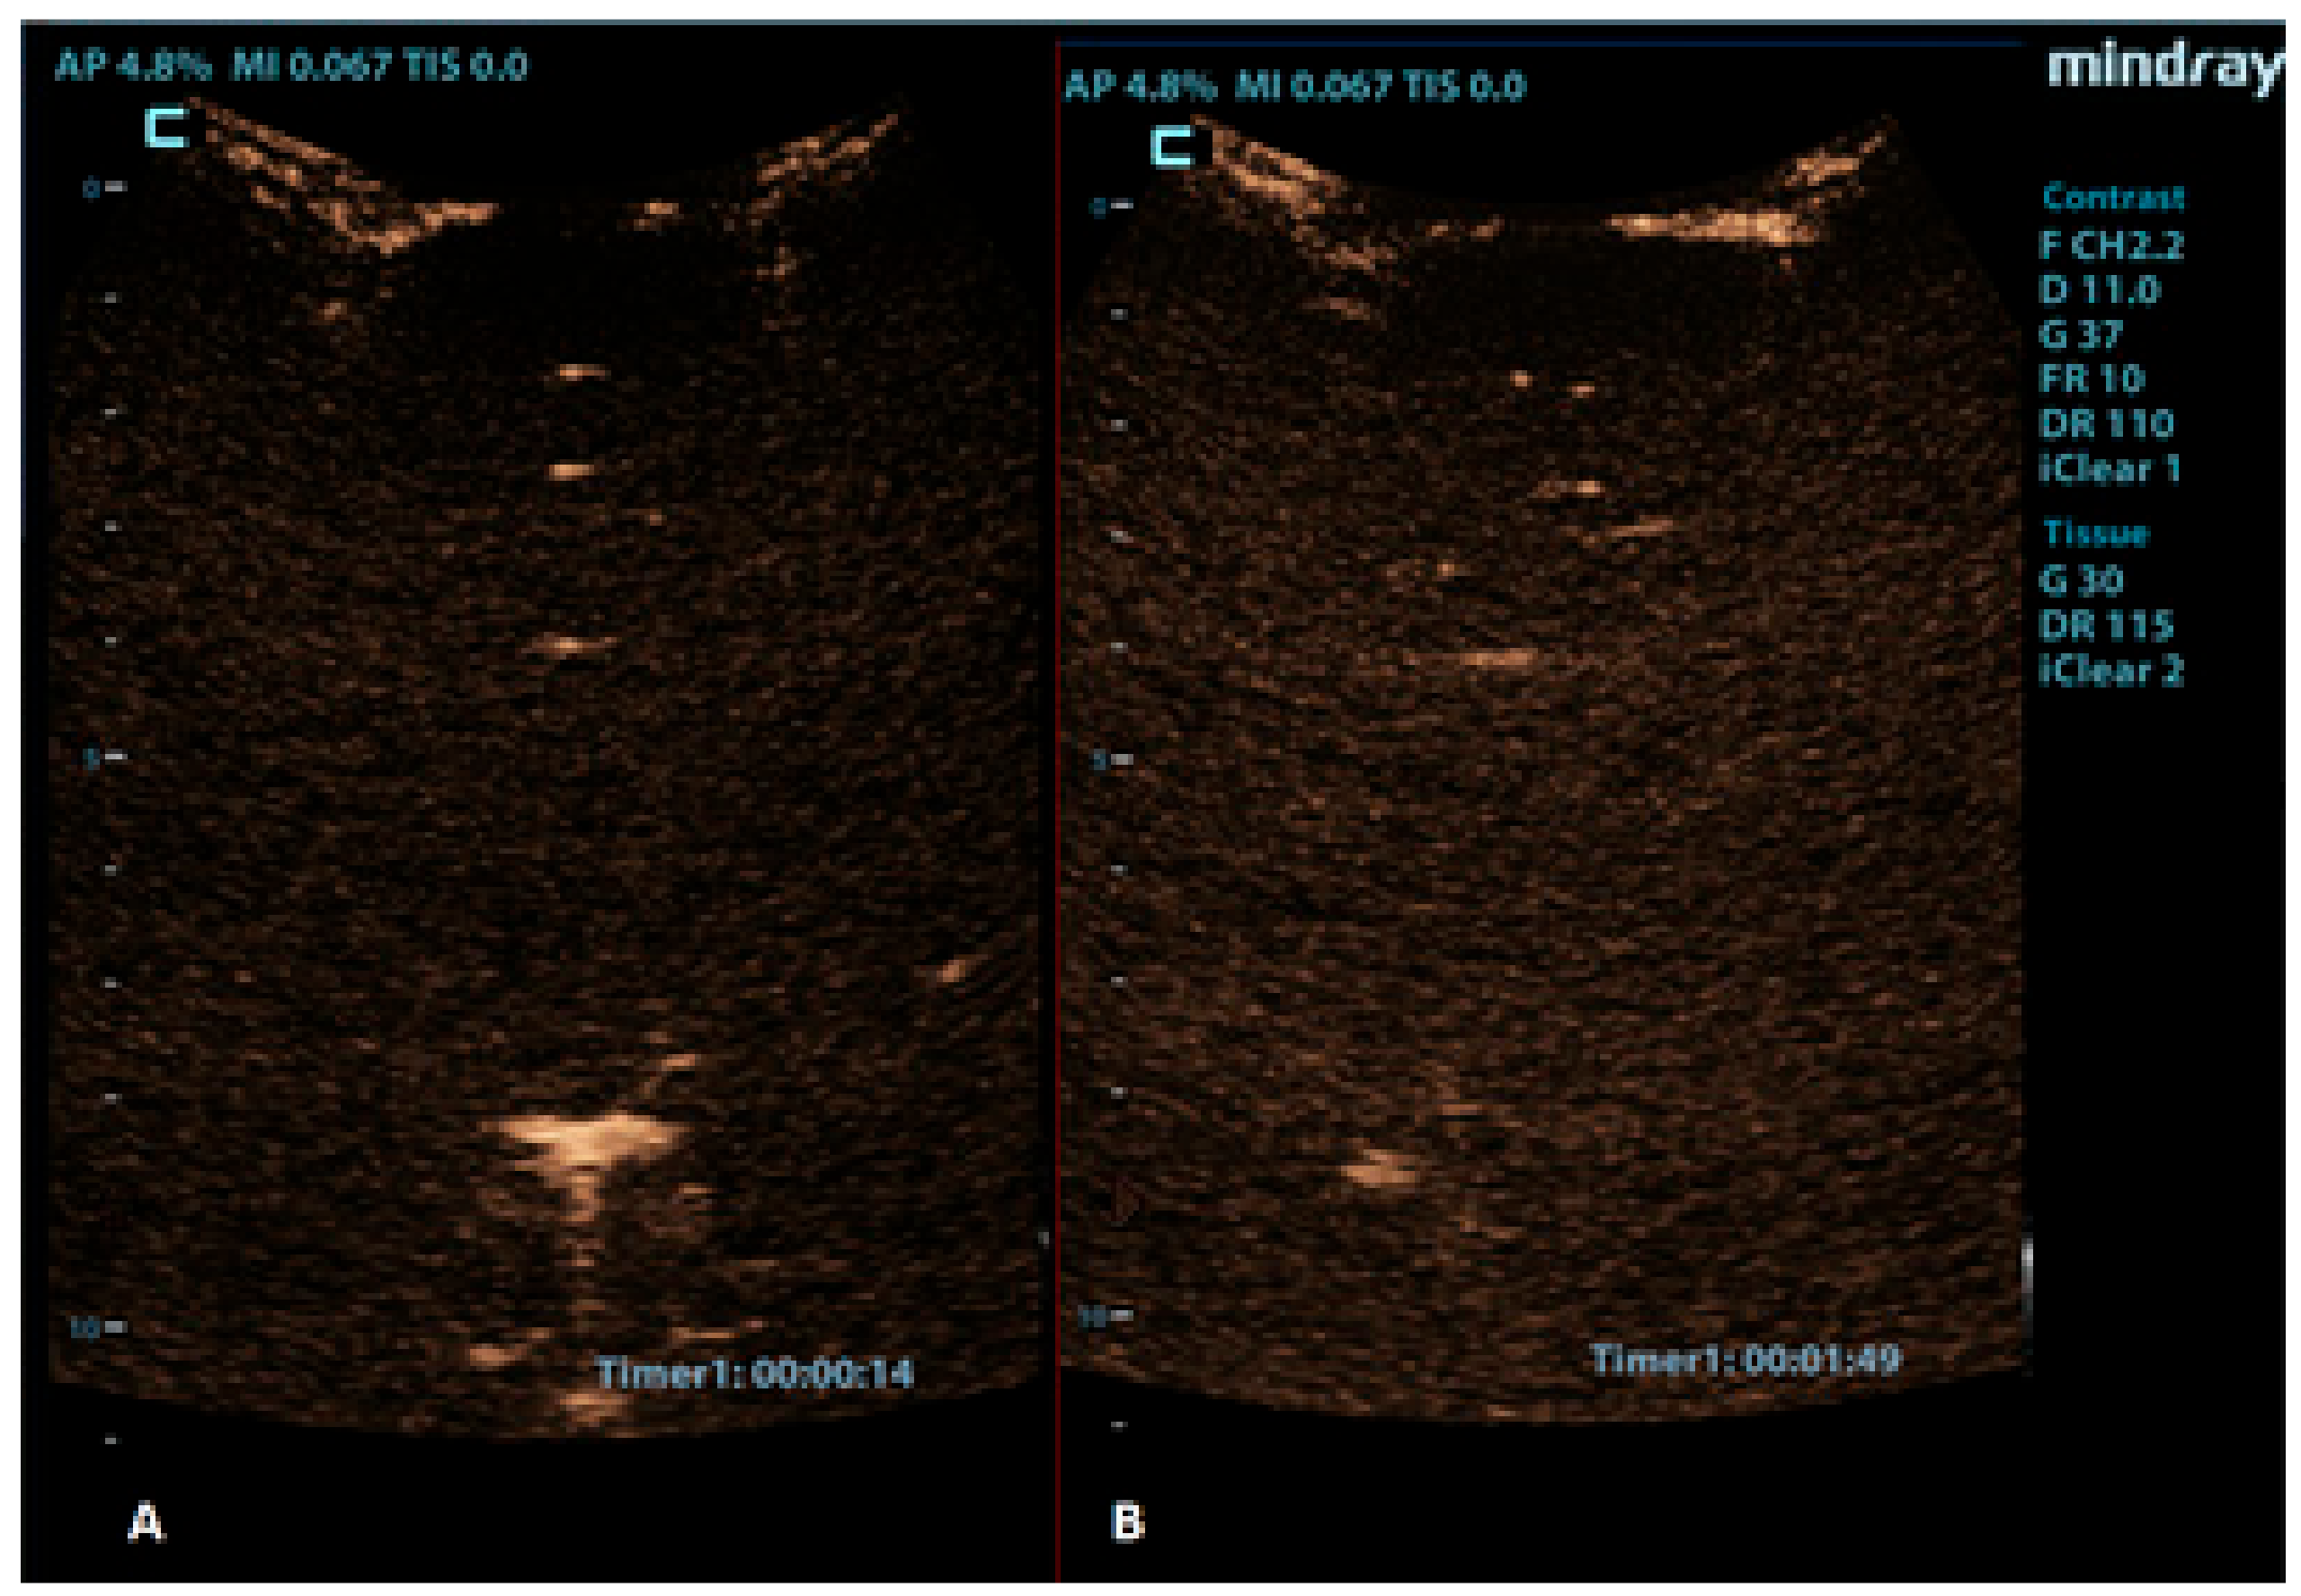

Figure 6.

A 2-month-old boy with acute lymphoblastic leukaemia and candida sepsis. Slowly growing hyperechoic lesions were detected using a brain ultrasound. (A) The sagittal CEUS image of the brain at 54 s after the application of contrast agent shows high signal intensity only at the rim of the lesion (crosses). Candida micro-abscesses were suspected and later confirmed using a brain MRI scan. (B) A sagittal reference grayscale ultrasound image shows a small hyperechoic lesion (plusses).